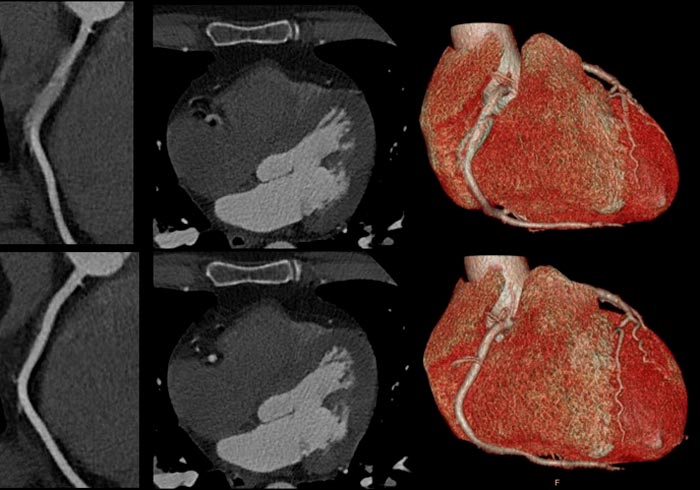

Los estudios tradicionales como el ecocardiograma o la tomografía no suelen mostrar los problemas cardiacos que se desarrollan al haber padecido COVID-19 sino hasta que deformaciones como la miocarditis o la pericarditis evolucionaron como deformaciones más severas.

Al hacer un estudio de Tomografía Computarizada de seguimiento, tras seis meses de haber padecido COVID-19, se reveló que el 35% de un grupo de 114 pacientes tenía anomalías que indicaban un daño permanente en los pulmones, el corazón también presenta daños que se pueden tratar a tiempo cuando se cuenta con un diagnóstico oportuno.

En muchas ocasiones las herramientas que se tienen para detectar daños en el corazón no son exactas en las métricas que proporcionan a los especialistas, ya que el factor humano interviene, por ello se ha buscado el desarrollo de herramientas con Inteligencia Artificial que permitan lecturas puntuales de la forma que actualmente tiene un órgano como el corazón.

Philips desarrolló tecnología de ultrasonidos que permite captar imágenes del corazón con la calidad que requiere un especialista para detectar deformaciones cardiacas o pulmonares con el tiempo que requiere un paciente para recibir tratamiento oportuno.